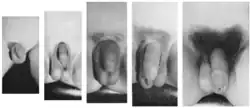

Pubarca

Pubarca[1] refere-se ao primeiro aparecimento de pelos pubianos em um adolescente. É uma das mudanças físicas da puberdade, e pode acontecer independentemente de uma puberdade completa. Geralmente ocorre como resultado do aumento dos níveis naturais e fisiológicos de andrógenos e em raras ocasiões pode ser causada pela exposição de uma criança a um esteroide anabolizante.[2]